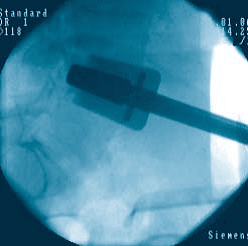

Watch the prodisc L Surgical Technique:

prodisc L Gallery

Click to enlarge image